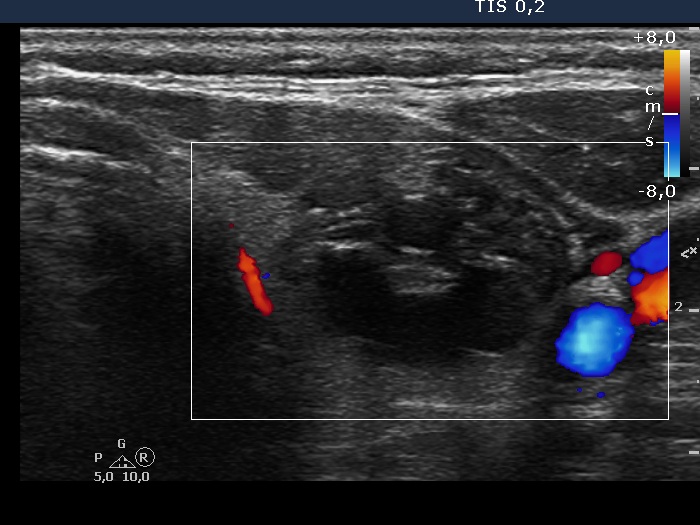

Right lobe, longitudinal scan

Left lobe, transverse view, color Doppler mode. The nodule is avascular.